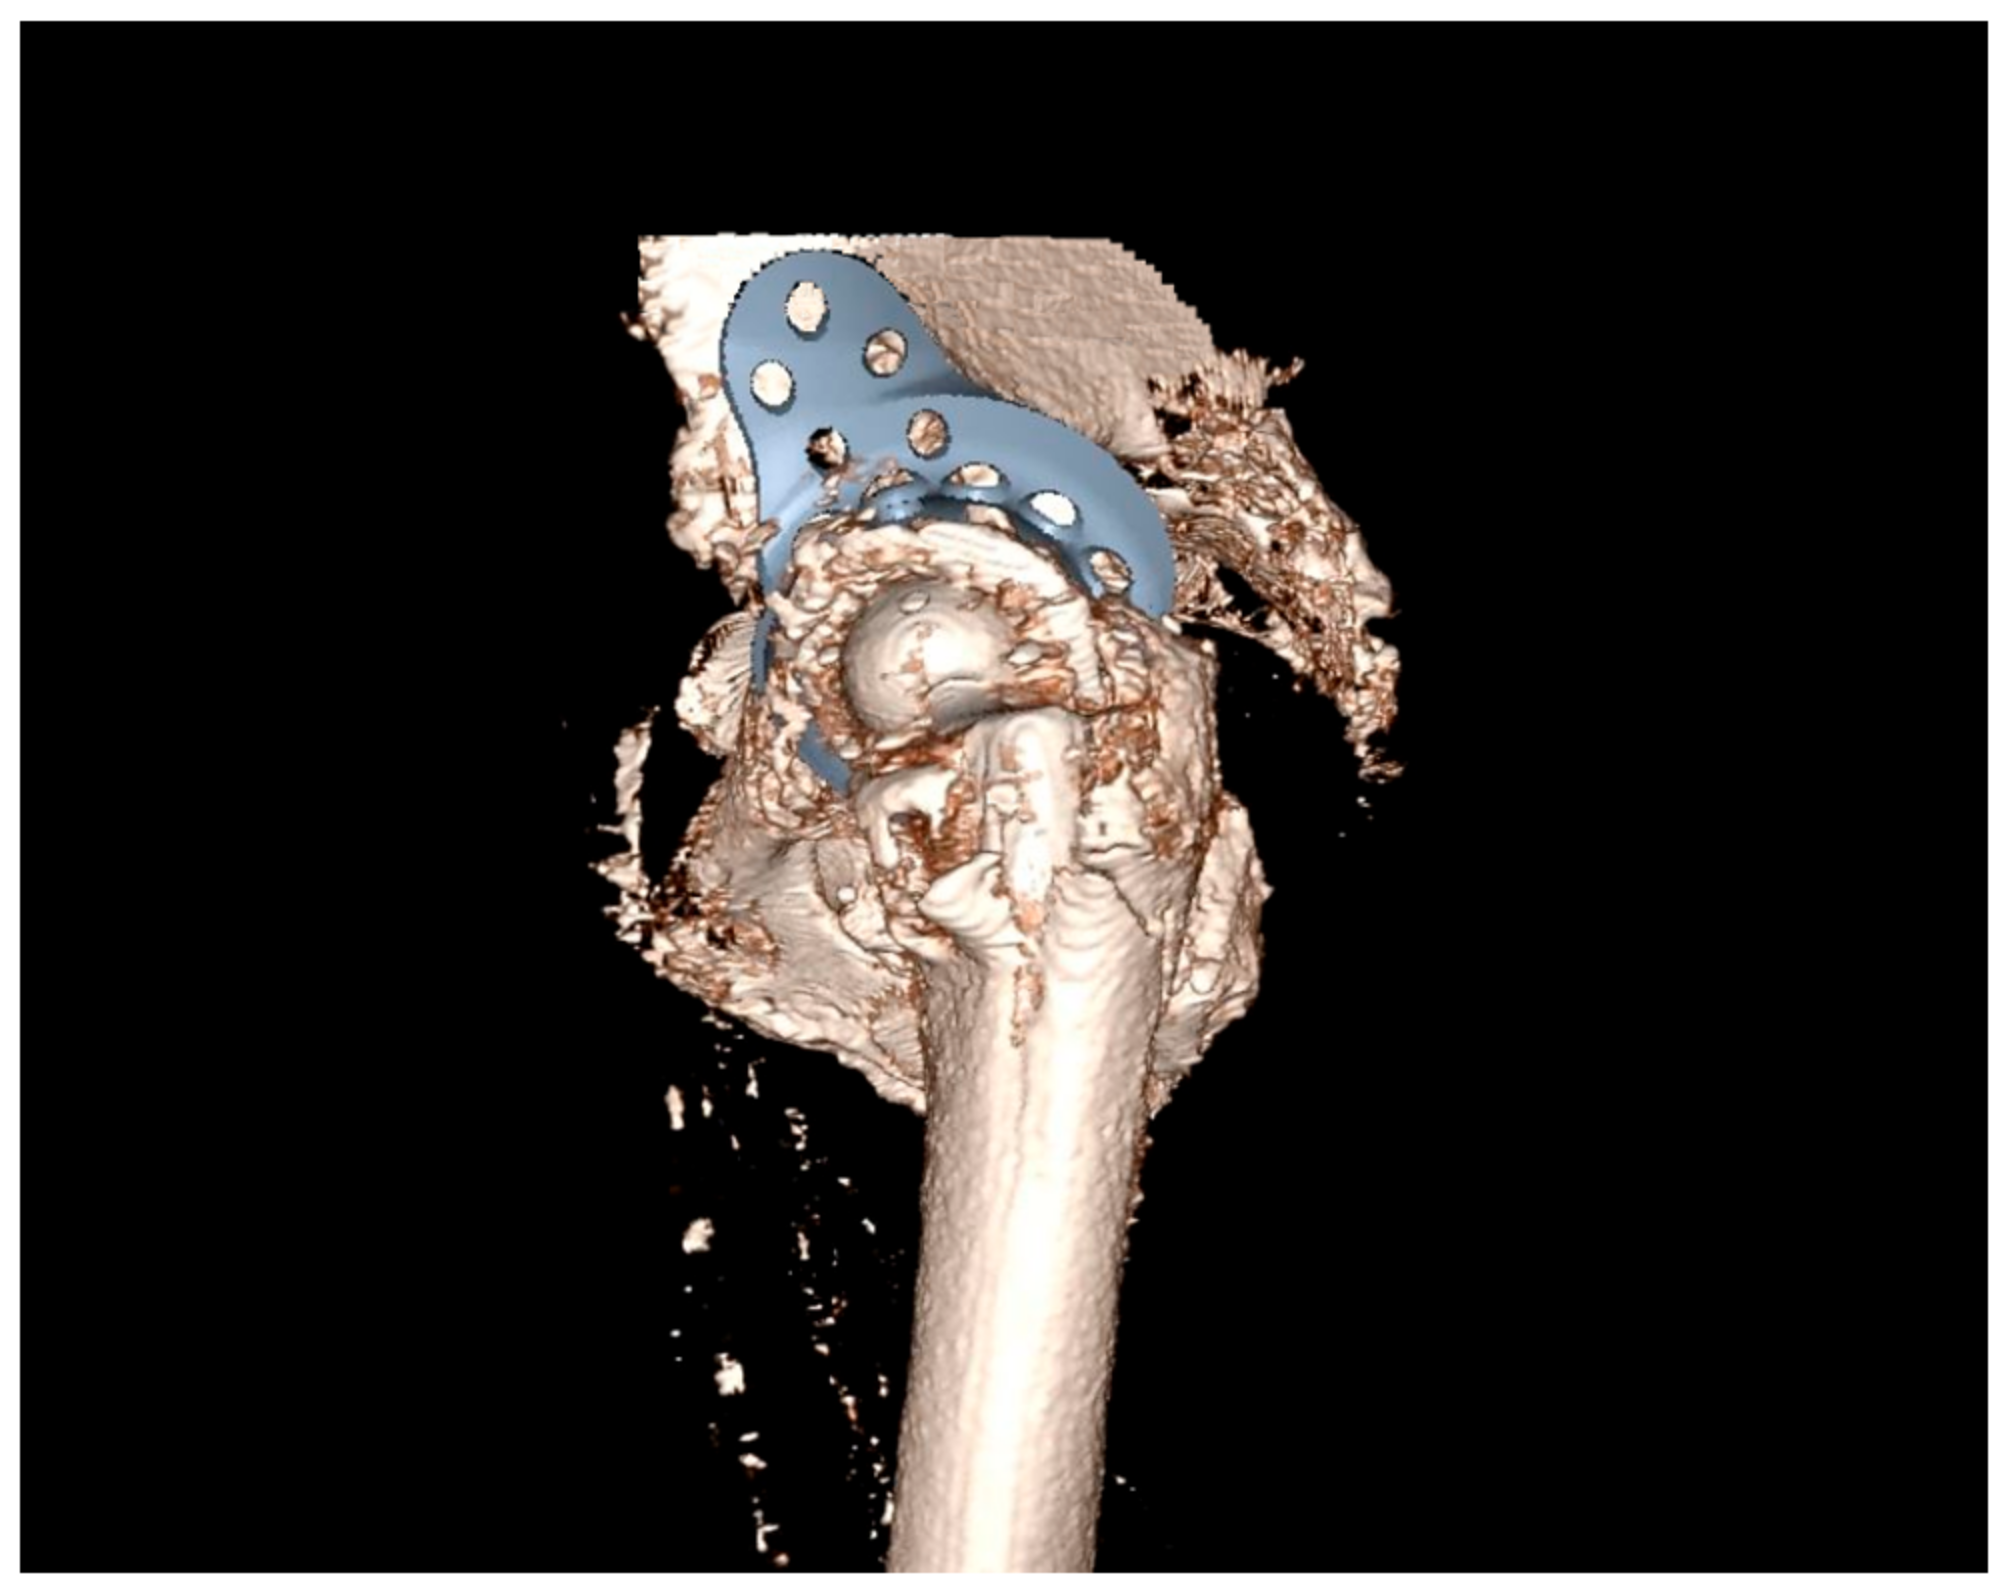

2.1. Preoperative Imaging

2.2. Digital Templating